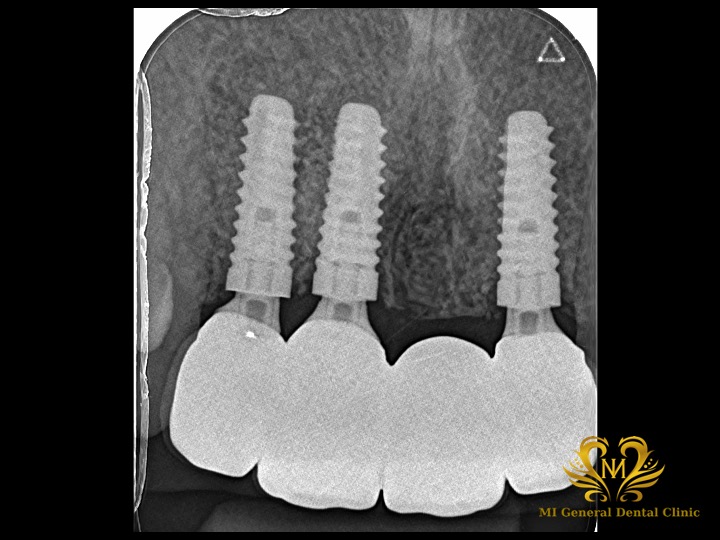

治療前

前歯4本がなく、CTでも本当に骨が残っていませんでした。

治療後

インプラント体と骨とセラミックスの被せ物が綺麗に合っています。